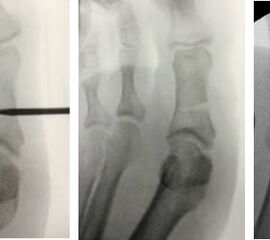

• Röntgenaufnahme des Fußes (unter Belastung) in dorsoplantarem und seitlichen Strahlengang (Abb. 3) und präoperative Fotodokumentation.

• Beurteilung des proximalen Gelenkflächenwinkels der Grundphalanx (Proximal Phalangeal Articular Angle, PPAA) des Hallux valgus interphalangeuswinkels (Hallux interphalangeus Angle, HIA) sowie des proximalen zum distalen Gelenksflächenwinkel (Proximal to Distal Phalangeal Articular Angle, PDPAA) 6789 (Abb. 2).

• 6 Wochen postoperativ Röntgenkontrolle in 2 Ebenen (dorsoplantar, lateral). Weitere Röntgenkontrolle in 2 Ebenen 6 Wochen später.

• Hallux valgus-interphalangeus-Rezidiv: Ein solches tritt auf, wenn bei der Osteotomie zuviel Knochen lateral verbleibt und die Spannung der lateralen Knochenbrücken ausreicht, den Osteotomiespalt wieder aufzudehnen. Eine zweite Ursache kann darauf beruhen, daß die Suturestrip Anlage nicht durchgeführt worden ist bzw. eine unzureichende Verbandsanlage postoperativ vorgenommen worden ist. Nach erfolgter knöcherner Konsolidierung ist eine neuerliche Korrektur mittels Reosteotomie möglich. In jedem Fall muß eine genaue radiologische Analyse zur optimalen Planung der Korrektur und die Verwendung einer Schraube empfohlen werden (siehe auch Minimalinvasive Chevron- und Akin-Osteotomie).